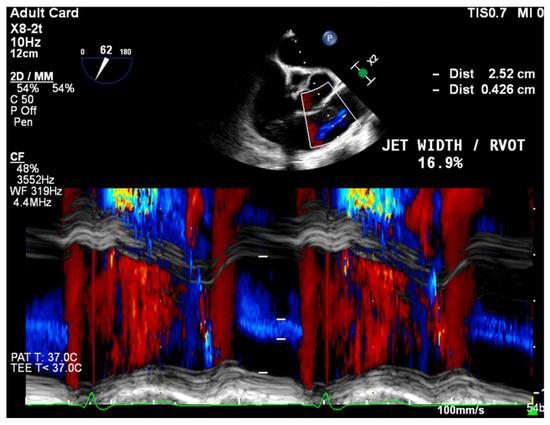

- PR Jet Width/RVOT Width: With >65% consistent with severe PR (Figure 3).